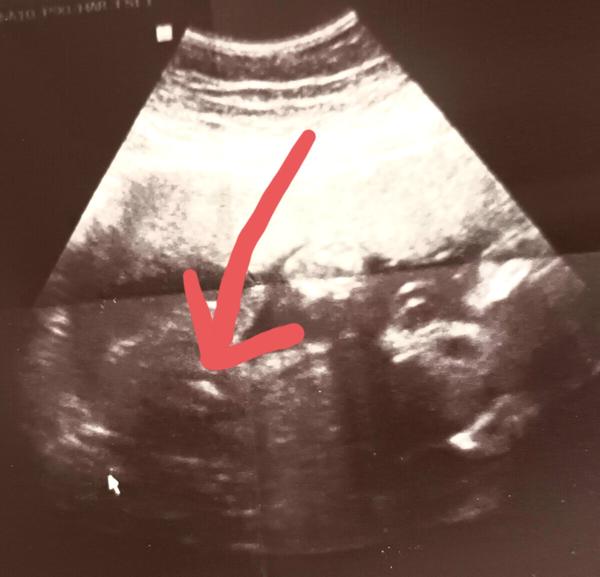

Poznáte pohlaví dítěte z této ultrazvukové fotky?

Jak se zjišťuje pohlaví dítěte?.